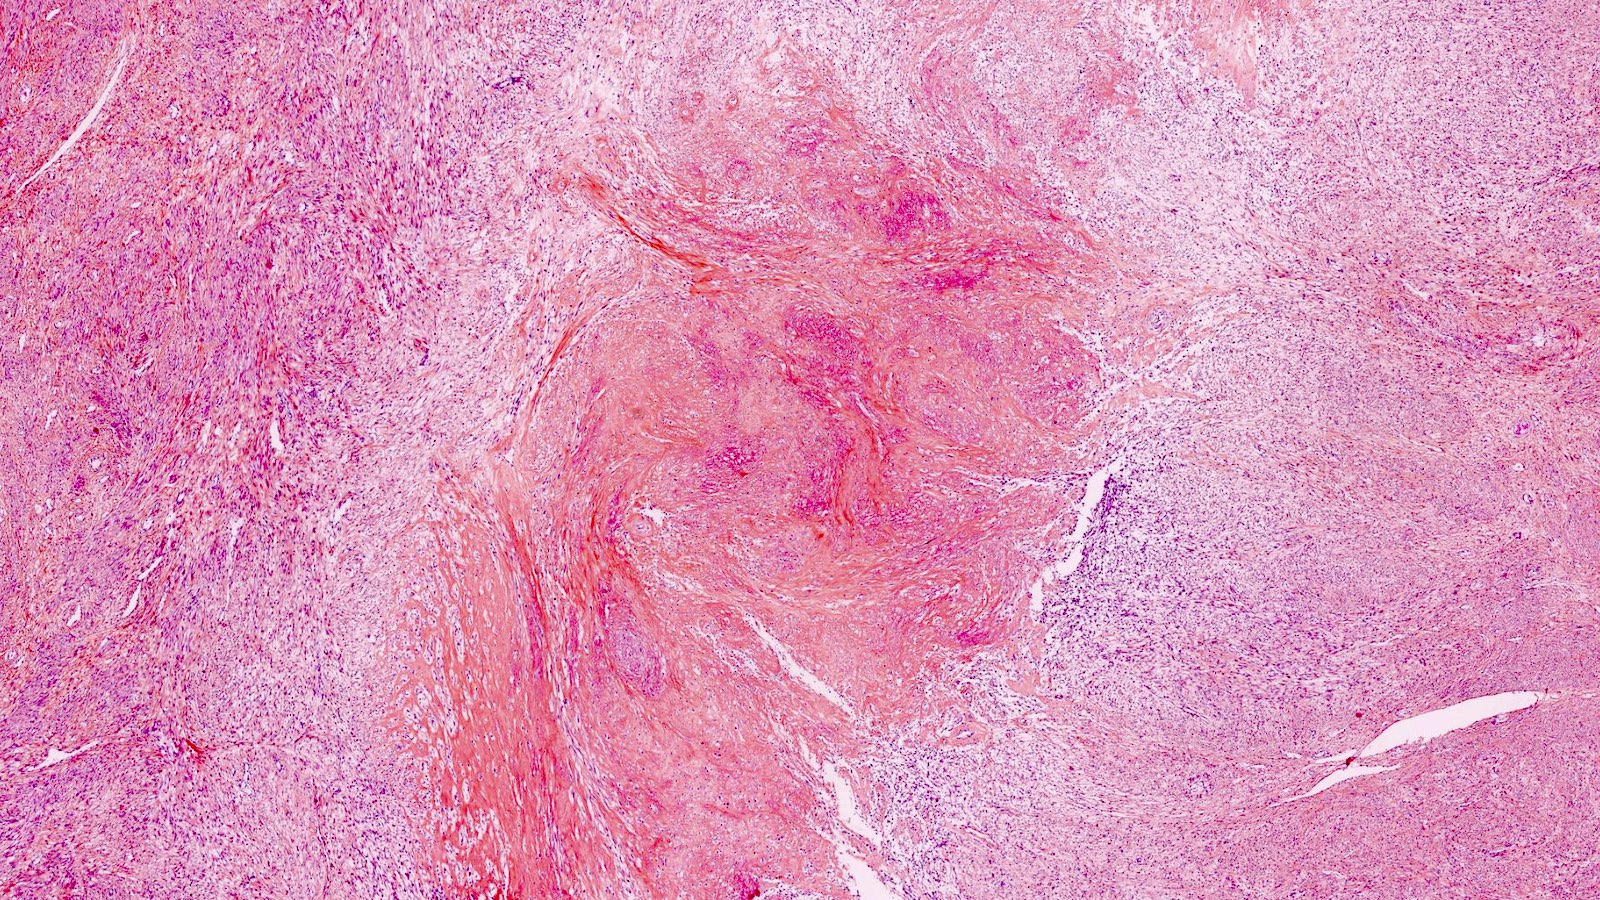

Myxoid Leiomyosarcoma. A, The Tumor Has An Infiltrative Growth Pattern

leiomyosarcoma myxoid tumor infiltrative growth leiomyoma necrosis tumors myometrium hypocellular abundant uterus eosin minimal atypia hematoxylin magnifications